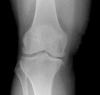

Fig 2

Frontal x ray of knee showing advanced osteoarthritis. Note the narrowing of the joint space, gas within the joint space, sclerosis, and bony spur formation along the margins of the distal femur and proximal tibia